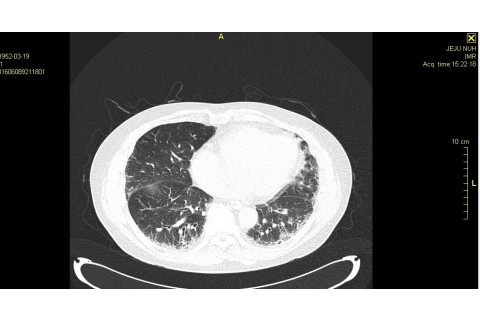

숨케어한의원에서는 전화예약을 받고 있습니다. 내원시 엑스레이, CT사진, 폐기능검사지를 가지고 오시면 자세한 상담이 가능합니다.